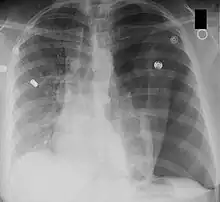

Pneumothorax shown on a chest x-ray. Air fills the space between the collapsed left lung and the chest wall.